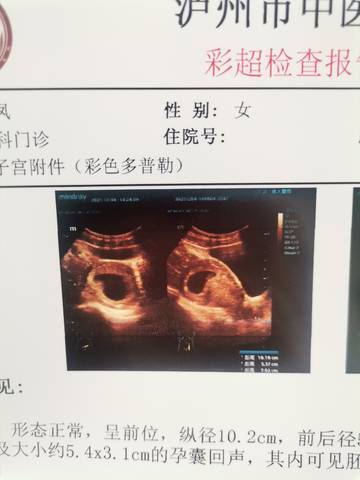

journal_insert_pic_1673509929journal_insert_pic_1673509950

亲爱的,图片里面的这个图片显示出来的话,只要孩子发育好就行了呀,反正你自己多注意,大部分是没事的。